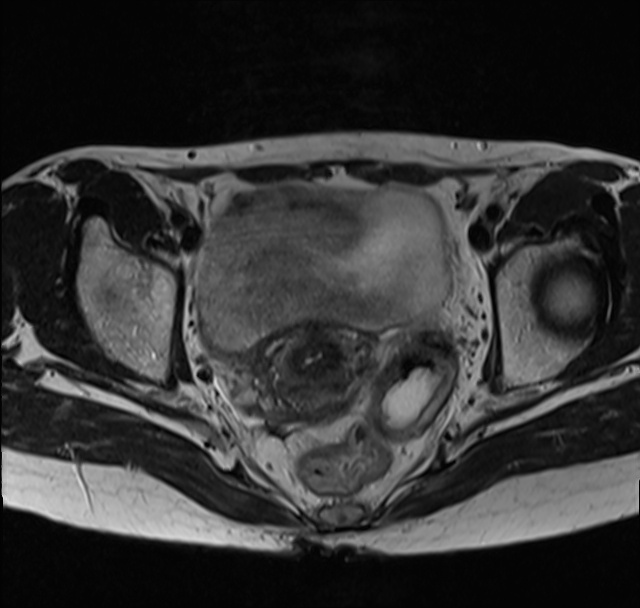

手术前CT照

怀着沉重的心情我回到家,儿子接过我的检查报告后隔天将我带到一家三甲医院进行再次检查,医生还给我做了盆腔包块穿刺术,确诊为卵巢浆液性癌,并且已经到了第四期。